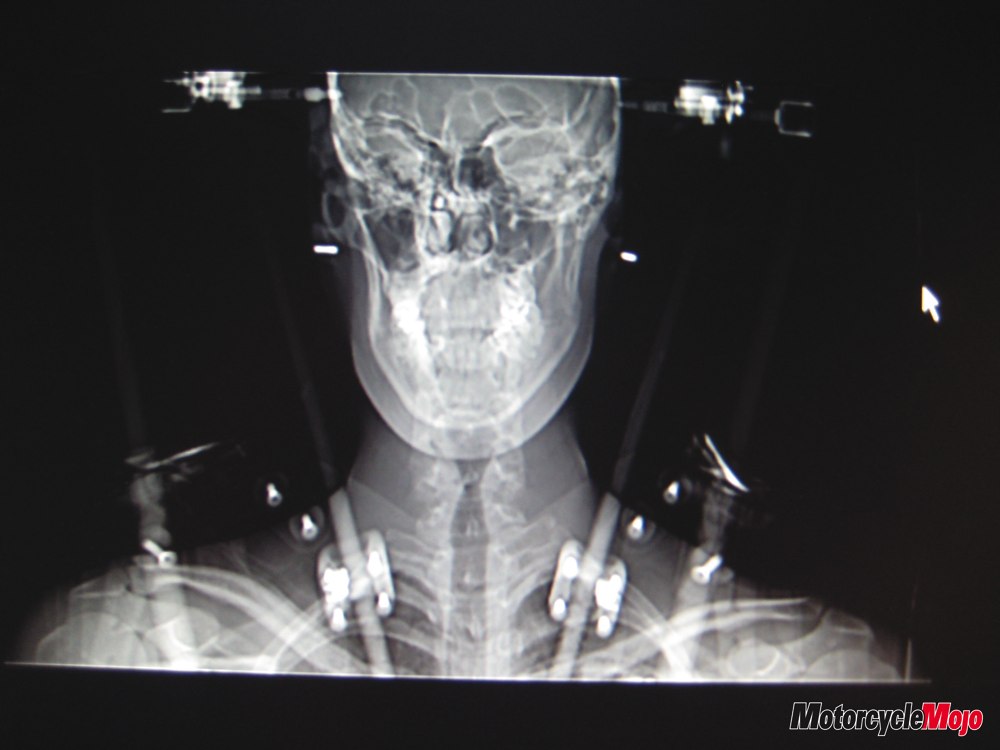

Josh had been wearing a size small helmet and by the time Bruce was done with him, he held a brand new XS Arai. It was this new helmet he was wearing when he crashed at Road Atlanta. After the crash, Josh got up and walked back to the pits with an obviously broken wrist and some neck pain. It was only later in the hospital that they found out that he had fractured the C2 vertebrae in his neck. Also known as a hangman’s fracture, this type of break in the neck could have easily resulted in full or partial paralysis. Galster was fitted with a halo, which he has been wearing for the last two months, and will continue to wear for another month, before moving to a hard brace. He is expected to make a full recovery.

After the crash, both Josh and I decided to go to the final round of the AMA at Laguna Seca to watch the races and to pay a special visit to Bruce himself. As Josh walked up in his halo, with his mom and I next to him, Bruce, with tears in his eyes, shook his hand and said, “great to see you Josh.” We all thanked Bruce profusely and made comments on the importance of wearing a good solid helmet, after all, it is your life that the helmet is responsible for.